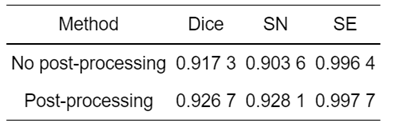

后处理检测结果:

对比图 13和14可知,经过后处理的测试集中仅有3例样本远离集群点,而未经过后处理的有7例样本远离集群点,说明后处理方法切实可行.后处理的脑肿瘤检测可视化结果如图 15所示,可以看出经过后处理的输出结果有效地抑制了非脑肿瘤病灶的假阳区域,经过后处理的检测结果与标注的金标准拟合程度更高.

有无增加后处理方法的测试集脑肿瘤检测其三种评价指标如表 2所示,经过后处理方法的Dice、SN和SE可以达到0.926 7、0.928 1和0.997 7,较未经后处理方法的结果分别提升了0.94%、2.45%和0.13%,进一步验证本文方法的有效性.

表 2 增加后处理后三种评价指标对比